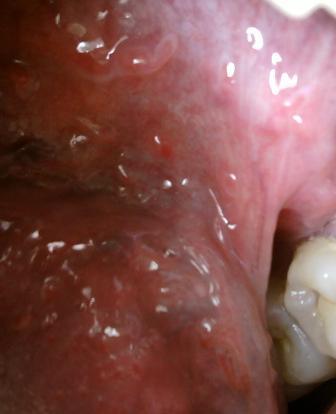

尖锐湿疣病情恶化之后什么样子初期病情症状表现为淡红色的小丘疹,不及时诊治,病情就会加重,湿疣体体积会增大,数目也会随之增多,而且在发病过程中还往往会伴随有瘙痒,疼痛的感觉。并且还会诱发其他一系列的并发症。